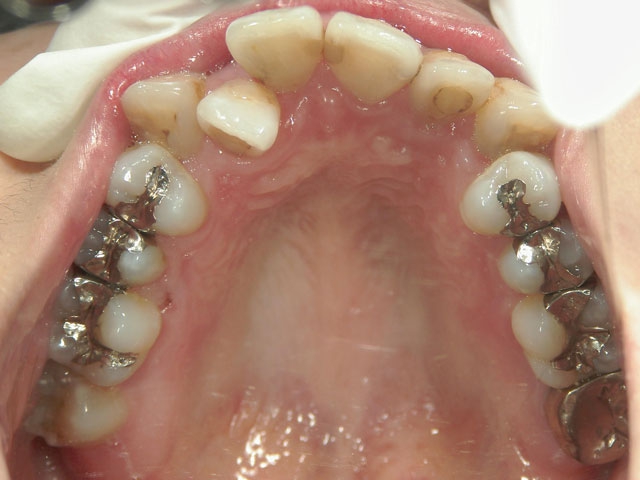

矯正歯科 治療前矯正歯科 治療前

28歳女性 浜松市中区在住

治療期間2年6ヶ月

矯正歯科 治療前 外科手術併用(コルチコトミー)、非抜歯